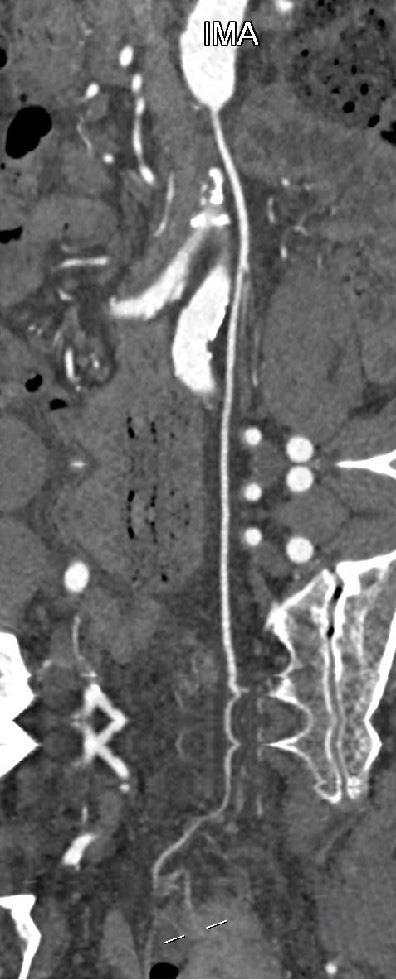

• 计算机体层摄影血管造影在腹腔镜结肠癌根治术前评估中的应用效果

摘要:目的 分析计算机体层摄影血管造影(CTA)在腹腔镜结肠癌根治术前评估中的应用效果。方法 回顾性分析2021年1月-2024年2月于该院接受腹腔镜结肠癌根治术的120例患者的临床资料。其中,60例行常规腹部CT和CTA,60例行磁共振成像(MRI)。以术后病理为金标准,判断CTA对临床T分期与术后病理的一致性,以及评估肿瘤是否侵犯肠系膜血管和周围组织的准确度。结果 术前CTA诊断T分期的准确率为95.00%(57/60),一致性好(Kappa = 0.925,P < 0.05);术前MRI诊断结肠癌T分期的准确率为98.33%(59/60),两者比较,差异无统计学意义(χ2 = 0.26,P > 0.05)。CTA预判肿瘤是否累及肠系膜上动脉、肠系膜上静脉、肠系膜下动脉、肠系膜下静脉、腹主动脉、肾动脉、肾静脉和脾动脉等血管,与术后病理的一致性好。特别是在预测肠系膜血管受累方面,CTA的敏感度为94.44%,特异度为95.83%,准确度高达95.00%。结论 对于行腹腔镜结肠癌根治术的患者,术前CTA不仅能清晰地显示结肠癌T分期,还能揭示肠系膜血管的走行和变异,以及肿瘤与周围组织的关系和侵犯程度,从而为手术规划提供强有力的支持,确保了腹腔镜手术的安全性,减少了不必要的手术风险。